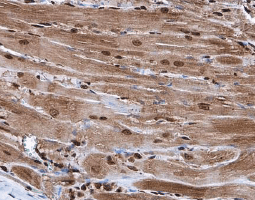

| 心臟的功能為泵驅動連續的血液柱通過脈管系統,心脏功能障碍和疾病可能是由于冠状动脉狭窄(动脉粥样硬化)、瓣膜性心脏病、影响心肌的心肌病、由于传导受损引起的心律失常以及感染或炎症过程(例如心内膜炎、心肌炎或心包炎), 心脏和血管疾病的临床和社会负担使心血管生物学研究成为重中之重。 |